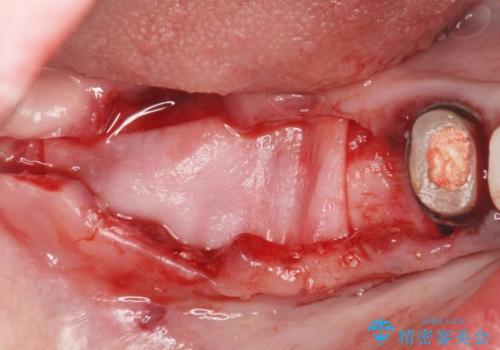

虫歯に伴い歯槽骨の吸収も見られたので造骨後、インプラントを用いて咬合機能を回復します。

また、機能後のインプラント周囲の清掃性を高めるため遊離歯肉移植術を行っています。